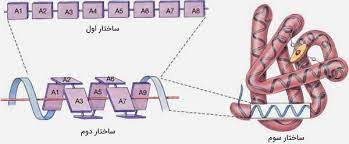

قیمت: 42٬000 تومان - دسته بندی فایل: پاورپوینتپاورپوینت تعیین ساختار سه بعدی پروتئین بر اساس توالی اسیدهای آمینه

فروش ویژه پاورپوینت حرفه ای تعیین ساختار سه بعدی پروتئین بر اساس توالی اسیدهای آمینه با تخفیف استثنایی فقط 54 هزار تومان تعداد اسلاید: 18 اسلاید